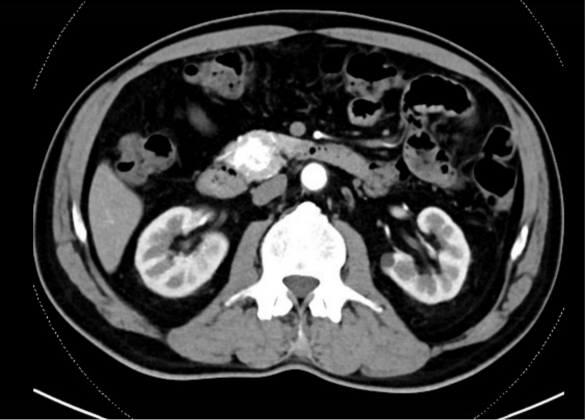

患者杨先生因“上腹部疼痛不适1月余”至扬州大学附属医院肝胆外科副主任、主任医师陶立德团队专家门诊就诊,查腹部CT结果检查结果示“胰头部占位”,予收住入院进一步诊治。入院后完善相关检查,认真评估患者肿瘤情况,考虑为胰腺神经内分泌肿瘤。

该患者肿瘤位于胰头部,治疗难度很大。扬大附院肝胆外科、影像科、麻醉科、消化内科、内分泌科等为其联合施行了多学科联合诊疗(MDT)。经术前精准评估,最终拟定两种手术方案进行比较选择:第一种方案是按传统手术方式施行保留幽门的胰十二指肠切除术,手术需切除十二指肠、部分胆总管、胆囊、胰头等,并完成胃肠、胰肠、胆肠等三处吻合,但该手术存在围手术期并发症多、患者术后会出现消化道功能障碍、营养不良等状况,影响生活质量,通常适用于预期生存期短的恶性肿瘤患者。第二种方案,施行胰头部分切除手术,即仅切除肿瘤及周围胰腺组织,术中完整保留胆管、十二指肠,避免胰管损伤,该方案优点在于在减少术中出血量、缩短手术时间、保护胰腺分泌功能等,预后远期效果优于前者。